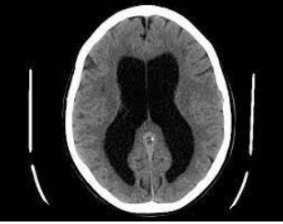

Imagem de TC: hidrocefalia